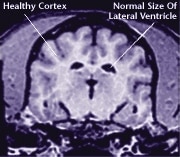

노화는 반려견의 삶에서 일어나는 자연스러운 일부분입니다. 반려견은 나이가 들어감에 따라 평소와 다른 행동을 보이기 시작합니다. 노화는 뇌를 비롯한 반려견의 몸 전체에 문제를 유발시키고 이로 인해 반려견의 행동에도 변화가 일어날 수 있습니다.

![]() Healthy Older Brain | ![]() Older Brain with Damage |

| MRI scans show loss of brain tissue in affected dogs. Note: MRI scans are not harmful to dogs. | |